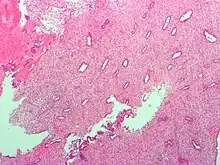

![]() Endometrium in the proliferative phase | |

The endometrium is the inner epithelial layer, along with its mucous membrane, of the mammalian uterus. It has a basal layer and a functional layer: the basal layer contains stem cells which regenerate the functional layer.[1] The functional layer thickens and then is shed during menstruation in humans and some other mammals, including apes, Old World monkeys, some species of bat, the elephant shrew[2] and the Cairo spiny mouse.[3] In most other mammals, the endometrium is reabsorbed in the estrous cycle. During pregnancy, the glands and blood vessels in the endometrium further increase in size and number. Vascular spaces fuse and become interconnected, forming the placenta, which supplies oxygen and nutrition to the embryo and fetus.[4][5] The speculated presence of an endometrial microbiota[6] has been argued against.[7][8]

The endometrium consists of a single layer of columnar epithelium plus the stroma on which it rests. The stroma is a layer of connective tissue that varies in thickness according to hormonal influences. In the uterus, simple tubular glands reach from the endometrial surface through to the base of the stroma, which also carries a rich blood supply provided by the spiral arteries. In women of reproductive age, two layers of endometrium can be distinguished. These two layers occur only in the endometrium lining the cavity of the uterus, and not in the lining of the fallopian tubes where a potentially life-threatening ectopic pregnancy may occur nearby.[4][5]